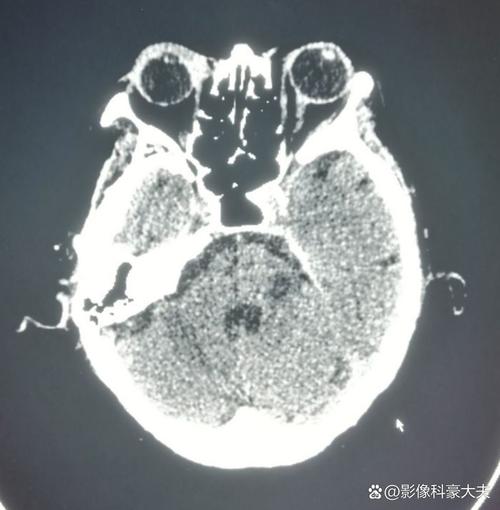

(图片来源网络,侵删)